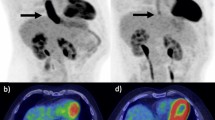

The potential predictors of pCR estimated by univariate and multivariate analyses are shown in Table 2. Multivariate analyses identified four independent predictors for pCR, including pre-OP NLR < 5.4 [OR 11.179; 95% CI 8.385–13.495; p = 0.003], NLR change (ΔNLR) < 3 [OR 4.891; 95% CI 2.274–9.180; p = 0.005], changes in SUV (ΔSUV) > 7.2 [OR 3.033; 95% CI 1.354–6.791; p = 0.007], and SUV changes ratio (ΔSUV ratio) > 58% [OR 3.585; 95% CI 1.576–8.152; p = 0.002]. ROC curves for pre-OP NLR, ΔNLR, ΔSUV, and ΔSUV ratio in predicting pCR were plotted in Supplementary Information 1. The optimized cut-off values for pre-OP NLR and ΔNLR were 5.4 and 3, respectively. The best cut-off points for ΔSUV and ΔSUV ratio were 7.2 and 58%, respectively. The prediction efficacy of the inflammatory (pre-OP NLR and ΔNLR) and the tumor glucose metabolic factors (ΔSUV and ΔSUV ratio) are shown in Table 3 and 4. The distribution of ΔNLR and ΔSUV ratio in patients with or without pCR is shown in Fig. 1. ΔNLR showed the highest accuracy and NPV (84.3% and 90.3%, respectively). In tumor glucose metabolic markers, ΔSUV ratio showed great sensitivity and NPV (77.8% and 72.7%, respectively). Combined factors of inflammatory status (ΔNLR < 3) and tumor glucose metabolic marker (ΔSUV ratio > 58%) gave the best PPV for pCR (84.8%). Higher PPV had a lower risk of false positive for the prediction of pCR. The risk of pathological residual tumor was 21.5% if using only ΔNLR < 3. This risk could be reduced to 15.2% with the combination of ΔNLR < 3 and ΔSUV ratio > 58%. The odds ratio of combined condition of ΔNLR < 3 and ΔSUV ratio > 58% was 21.543 (95% CI 8.047–57.670). High ΔNLR and low ΔSUV ratio were associated with residual tumor after neoCRT [OR 11.333, 95% CI 3.196–40.184].